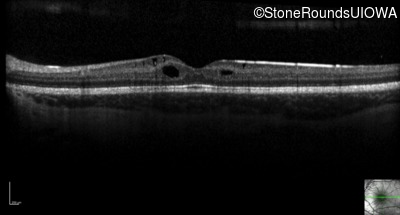

Optical Coherence Tomography - Right - 20/50

Exemplar / OCT Stack